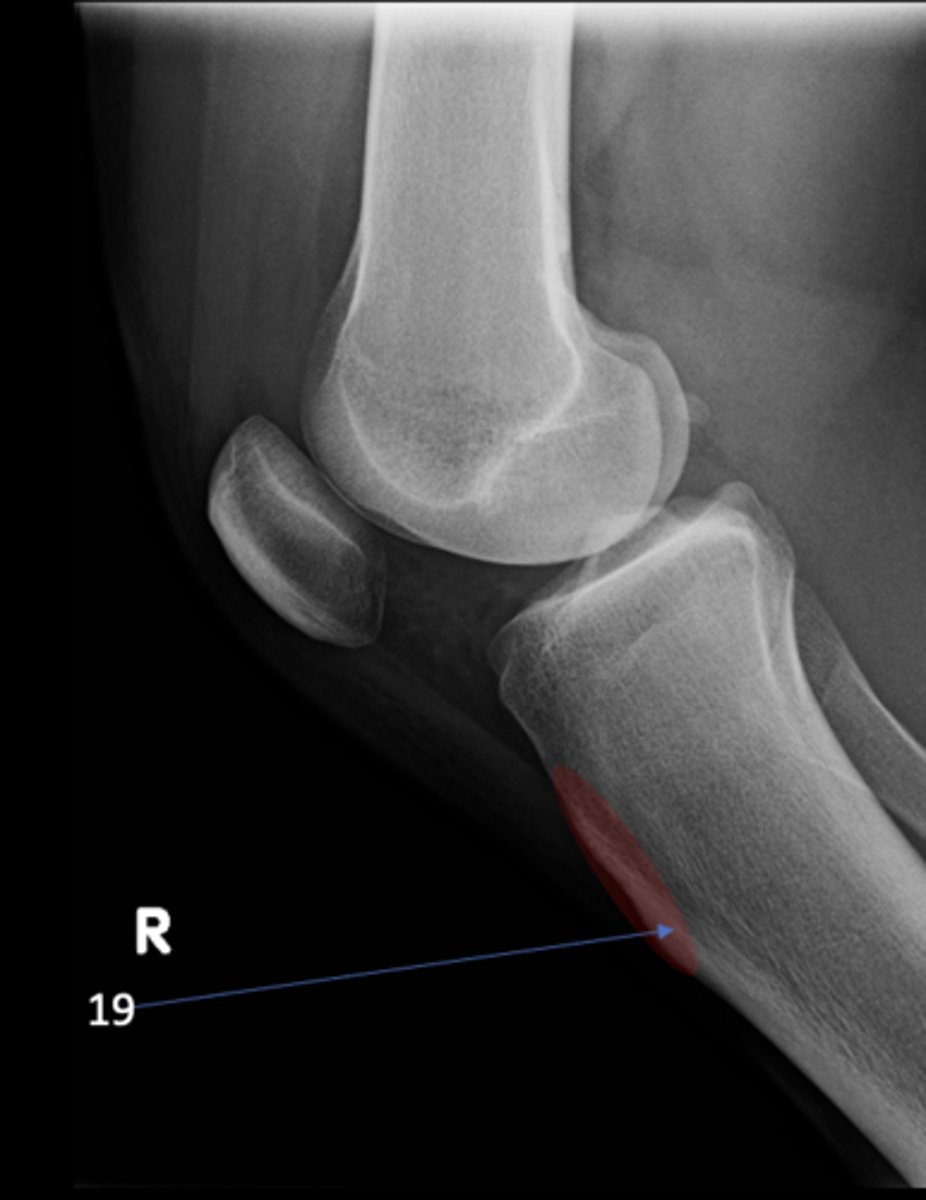

ID 9

<p>ID 9</p>

10

ID 19

<p>ID 19</p>